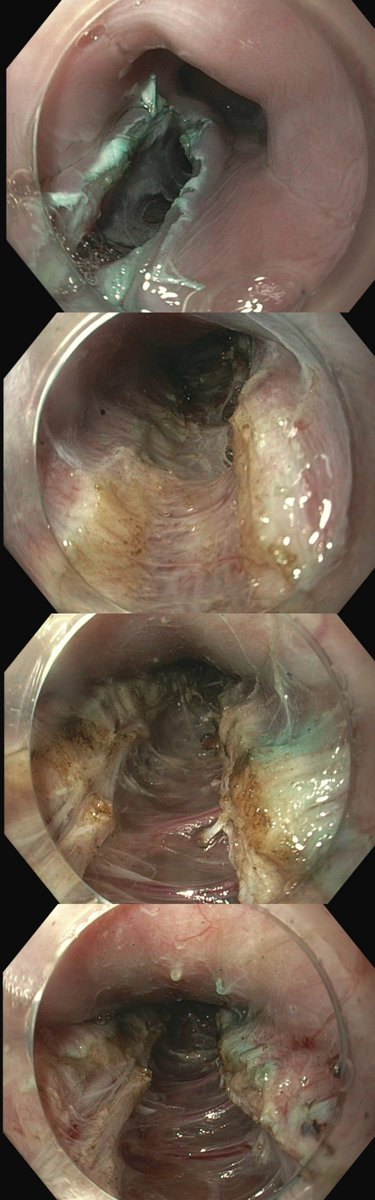

ESD ๐. 3cm BE with concerns for intramucosal ca on path removed en bloc. Excited to join @uams_GIHep and contribute to their already brilliant interventional endoscopy program @MaugarMD @SumantInamdar. Grateful to @shandrawes ๐๐ฝ๐๐ฝ๐๐ฝ @MuzaffarAkbar @Jean_Chalhoub @ASGEendoscopy